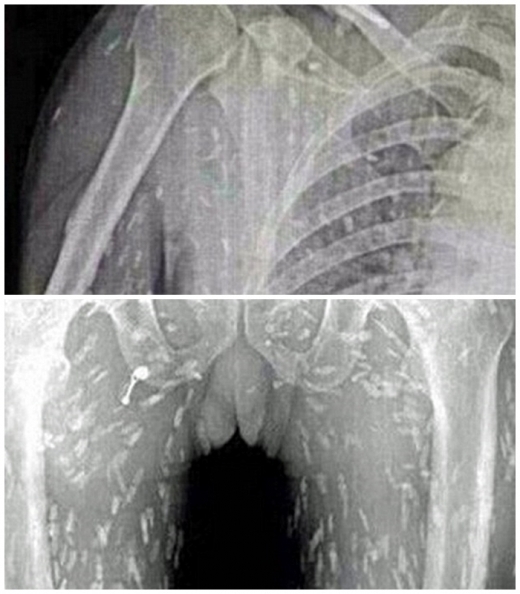

(혐오주의) 생선회 먹고 기생충이 온몸에 퍼진 남성

그냥 엑스레이사진인데 기생충이 많아요! 전 그닥 징그럽지는 않았는데 좀 소름돋긴했어요